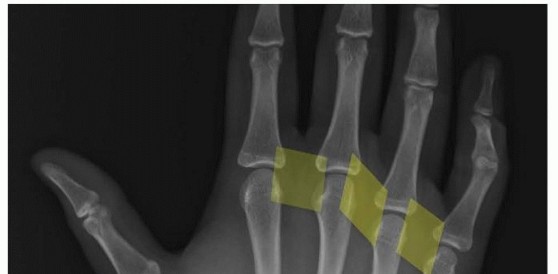

Operative Treatment of Finger Carpometacarpal Joint Fracture-Dislocations